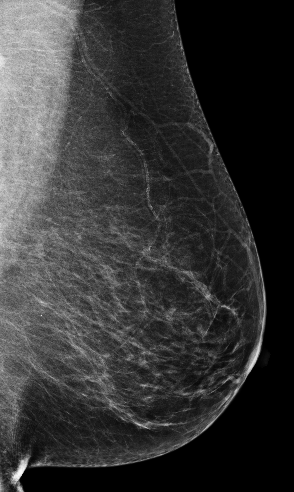

Masking refers to the phenomenon in which a tumor is hidden by the surrounding breast tissue, causing the cancer to be difficult or even impossible to discern with regular mammography, as seen in Figure 2. Masking can also result in large invasive cancers111We define large invasive cancers as those confirmed to have spread and be 2cm at time of diagnosis. – a small cancer may be difficult to discern in certain images, allowing it to grow to a more lethal size. Masking is correlated with breast density, as it has been shown that cancer in dense breasts is more likely to be missed during screening [5, 6, 7]. Density can be subjectively assessed by radiologists via the BI-RADS density standard (ACR) [8, 9], or measured by automated tools such as Libra [10]. These density measurements, however, do not perfectly correlate with masking potential. Radiologists consider the distribution and pattern of tissue when assessing masking potential, and have called for automated methods to assess the masking effect [11]. Until now, the question of exactly how masking potential should be quantified remains an open one, although some subjective notion has been added to certain categories of the most recent edition of BI-RADS density [12].

In this work, we introduce the CSAW-M dataset – a collection of over 10,000 mammographic images and associated masking assessments from experts. The assessments were graded by radiologists according to 8 levels of masking potential, as depicted in Figure 1, from easily assessed mammograms with low-masking potential (level 1) to difficult-to-assess examples with high-masking potential (level 8). This data can be used to train models capable of predicting masking potential from mammographic images in an ordinal classification setting.

The goal of the annotation procedure was to label each image with expert assessments of masking potential. Masking was quantized into 8 bins, or levels, as depicted in Figure 1, for the public training and test sets. Images in the private test set are fully sorted according to masking. Individually sorted examples provide a more granular assessment, but at the cost of increased annotation time. We opted for fine granularity on the private test set because (1) it allows for a more fine-grained assessment, and (2) it allowed us to identify robust initial bins555We use “bin” and “level” interchangeably to denote collections of images with similar masking potential. for the 8 masking levels in the public training/test sets. To represent the initial bins, we chose images personalized to each radiologist, but with highest agreement among the other experts. The benefit to this approach is that the starting point respects subjective assessments while at the same time choosing representative examples for each masking level.

We begin by considering the question how well do the experts agree w.r.t. masking potential? This is an important question to consider, as the main task is to emulate the median expert assessment. Table 3 shows experts have an AMAE ranging from 0.68 to 1.04. This suggests that, on average, individual experts are almost masking levels distant from the ground truth – a reasonable level of agreement. A more nuanced picture of expert agreement is given in Figure 5. Here, agreement between each expert, as well as the ground truth, is measured by Kendall’s . As a rule-of-thumb Kendall’s 0.3 indicates a strong association 666We refer the reader here for an interpretation of Kendall’s .. According to this rule, all experts have a strong association, although we can see that experts 1, 2, and 5 exhibit substantially higher agreement than experts 3 and 4. Interestingly, the experts who tended to agree more were also less experienced. Turning to the F1-scores in Table 3, it is clear that experts are in better agreement for low-masking cases than for high-masking cases. This suggests that high-masking potential is a generally less agreeable property than low-masking potential. Our findings on the public test set are mirrored in the private test set, provided in Appendix F. Examples of mammograms where experts agree and disagree are provided in Figure 4.

The models seem to be more correlated with Experts 1, 2, and 5, who agreed with each other more often (and the ground truth). Interestingly, our models were more correlated with each individual radiologist than any of their colleagues were (see the two rightmost columns in Figure 5). Please note that the cross-tabulation in Figure 5b is asymmetric because the number of mammograms placed into each masking level is different for each radiologist – i.e. the AMAE between two experts changes depending on which one is considered as the reference. In Figure 4, we provide several examples where the networks both agree and disagree with the experts. Figure 4(g) is an interesting case because the density is fairly low but experts rate it as high masking potential. Our models under-estimate the masking, suggesting they rely too heavily on general density cues.